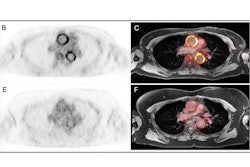

F-18 FDG PET/MRI is also helping to optimize axillary lymph node management, Dr. Daniela Ballerini, a radiologist in the Breast Radiology Unit at the IRCCS Ospedale San Raffaele in Milan, and colleagues stated in another EUSOBI 2025 presentation.

The Milan team evaluated the accuracy of hybrid F-18 FDG PET/MRI in detecting axillary lymph nodes macro-metastases, in order to safely evaluate in the future axillary surgery omission in selected early breast cancer patients, in a prospective interventional single-arm monocentric trial.

Between June 2020 and April 2024, the group recruited 246 patients with breast cancer (251 axillae evaluated due to five having bilateral disease) without nodal involvement on ultrasound and clinical examination. They were eligible for upfront surgery. All the patients underwent F-18 FDG PET/MRI before surgery. Two radiologists and two nuclear medicine physicians, all blinded, independently reviewed the images.

The mean (SD) age at surgery was 56.3 (10.7), and the mean (SD) tumor size was 17.5 (13) mm at final pathology, the authors wrote. Macrometastatic axillary lymph nodes were found at surgery in 61 cases (24.3%). F-18 FDG PET/MRI had identified 43 (70.5%) of these cases. The hybrid technique significantly outperformed both F-18 FDG PET and MRI alone, which identified 36 (59%; p = 0.016) and 25 (41%; p < 0.001) cases, respectively. Negative predictive value was higher for F-18 FDG PET/MRI (89.4%) than F-18 FDG PET (86.4%, p = 0.021) and MRI (82.9%, p < 0.001) alone.

Prior to surgery, F-18 FDG PET/MRI detected 70.5% of cases with macrometastatic axillary lymph nodes in patients with clinically negative axilla, with greater accuracy than F-18 FDG PET or MRI alone.